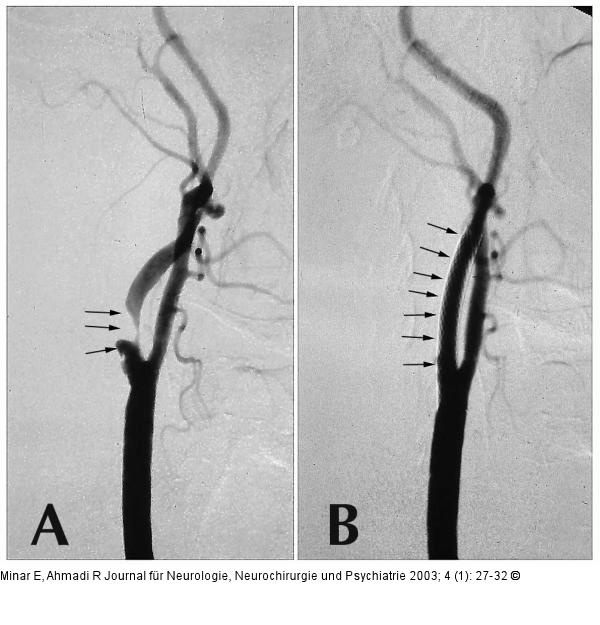

Abbildung 1A-B: Arteria carotic - Stenose - Stent A) Hochgradige symptomatische Stenose der A. carotis interna; B) gutes morphologisches Ergebnis nach erfolgreicher Stentangioplastie |

A) Hochgradige symptomatische Stenose der A. carotis interna; B) gutes morphologisches Ergebnis nach erfolgreicher Stentangioplastie |